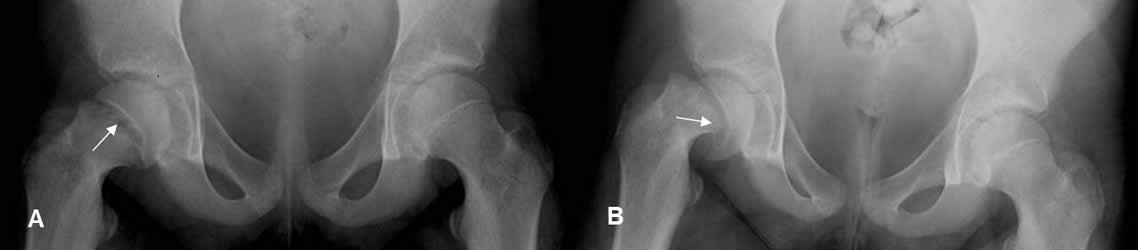

Fig 69. Salter tipo I.

A: Rx AP. Aumento del espacio en la placa de crecimiento derecha. Comparar con el lado contralateral.

B: Rx AP de control. Desplazamiento medial del núcleo de crecimiento, en relación con el cuello femoral.